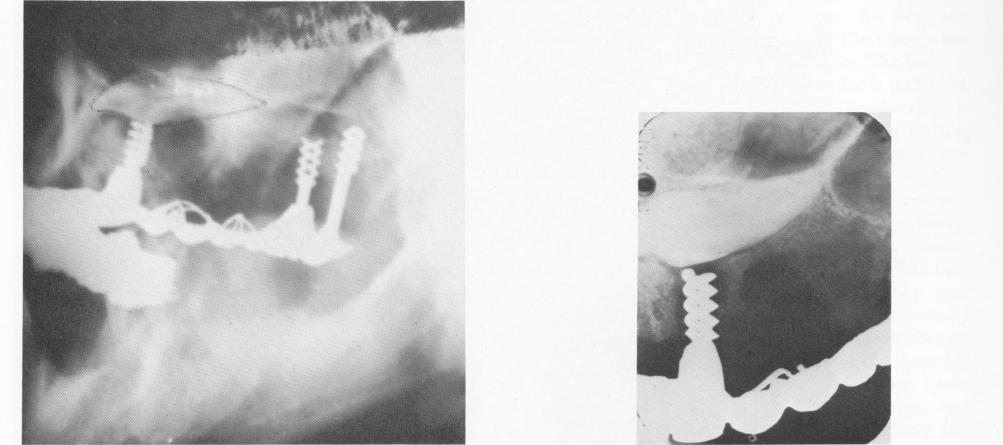

Fig. 4-28. A 2-year postoperative lateral plate shows that the two tuberosity implants were secure. (Impacted cuspid

Fig. 4-29. The implant below the impacted cuspid was failing.

1 Clinical view after prosthesis placed on Chercheve spiral-post implant

2 Lateral plate Xray shows two secure Chercheve spiral-post implants